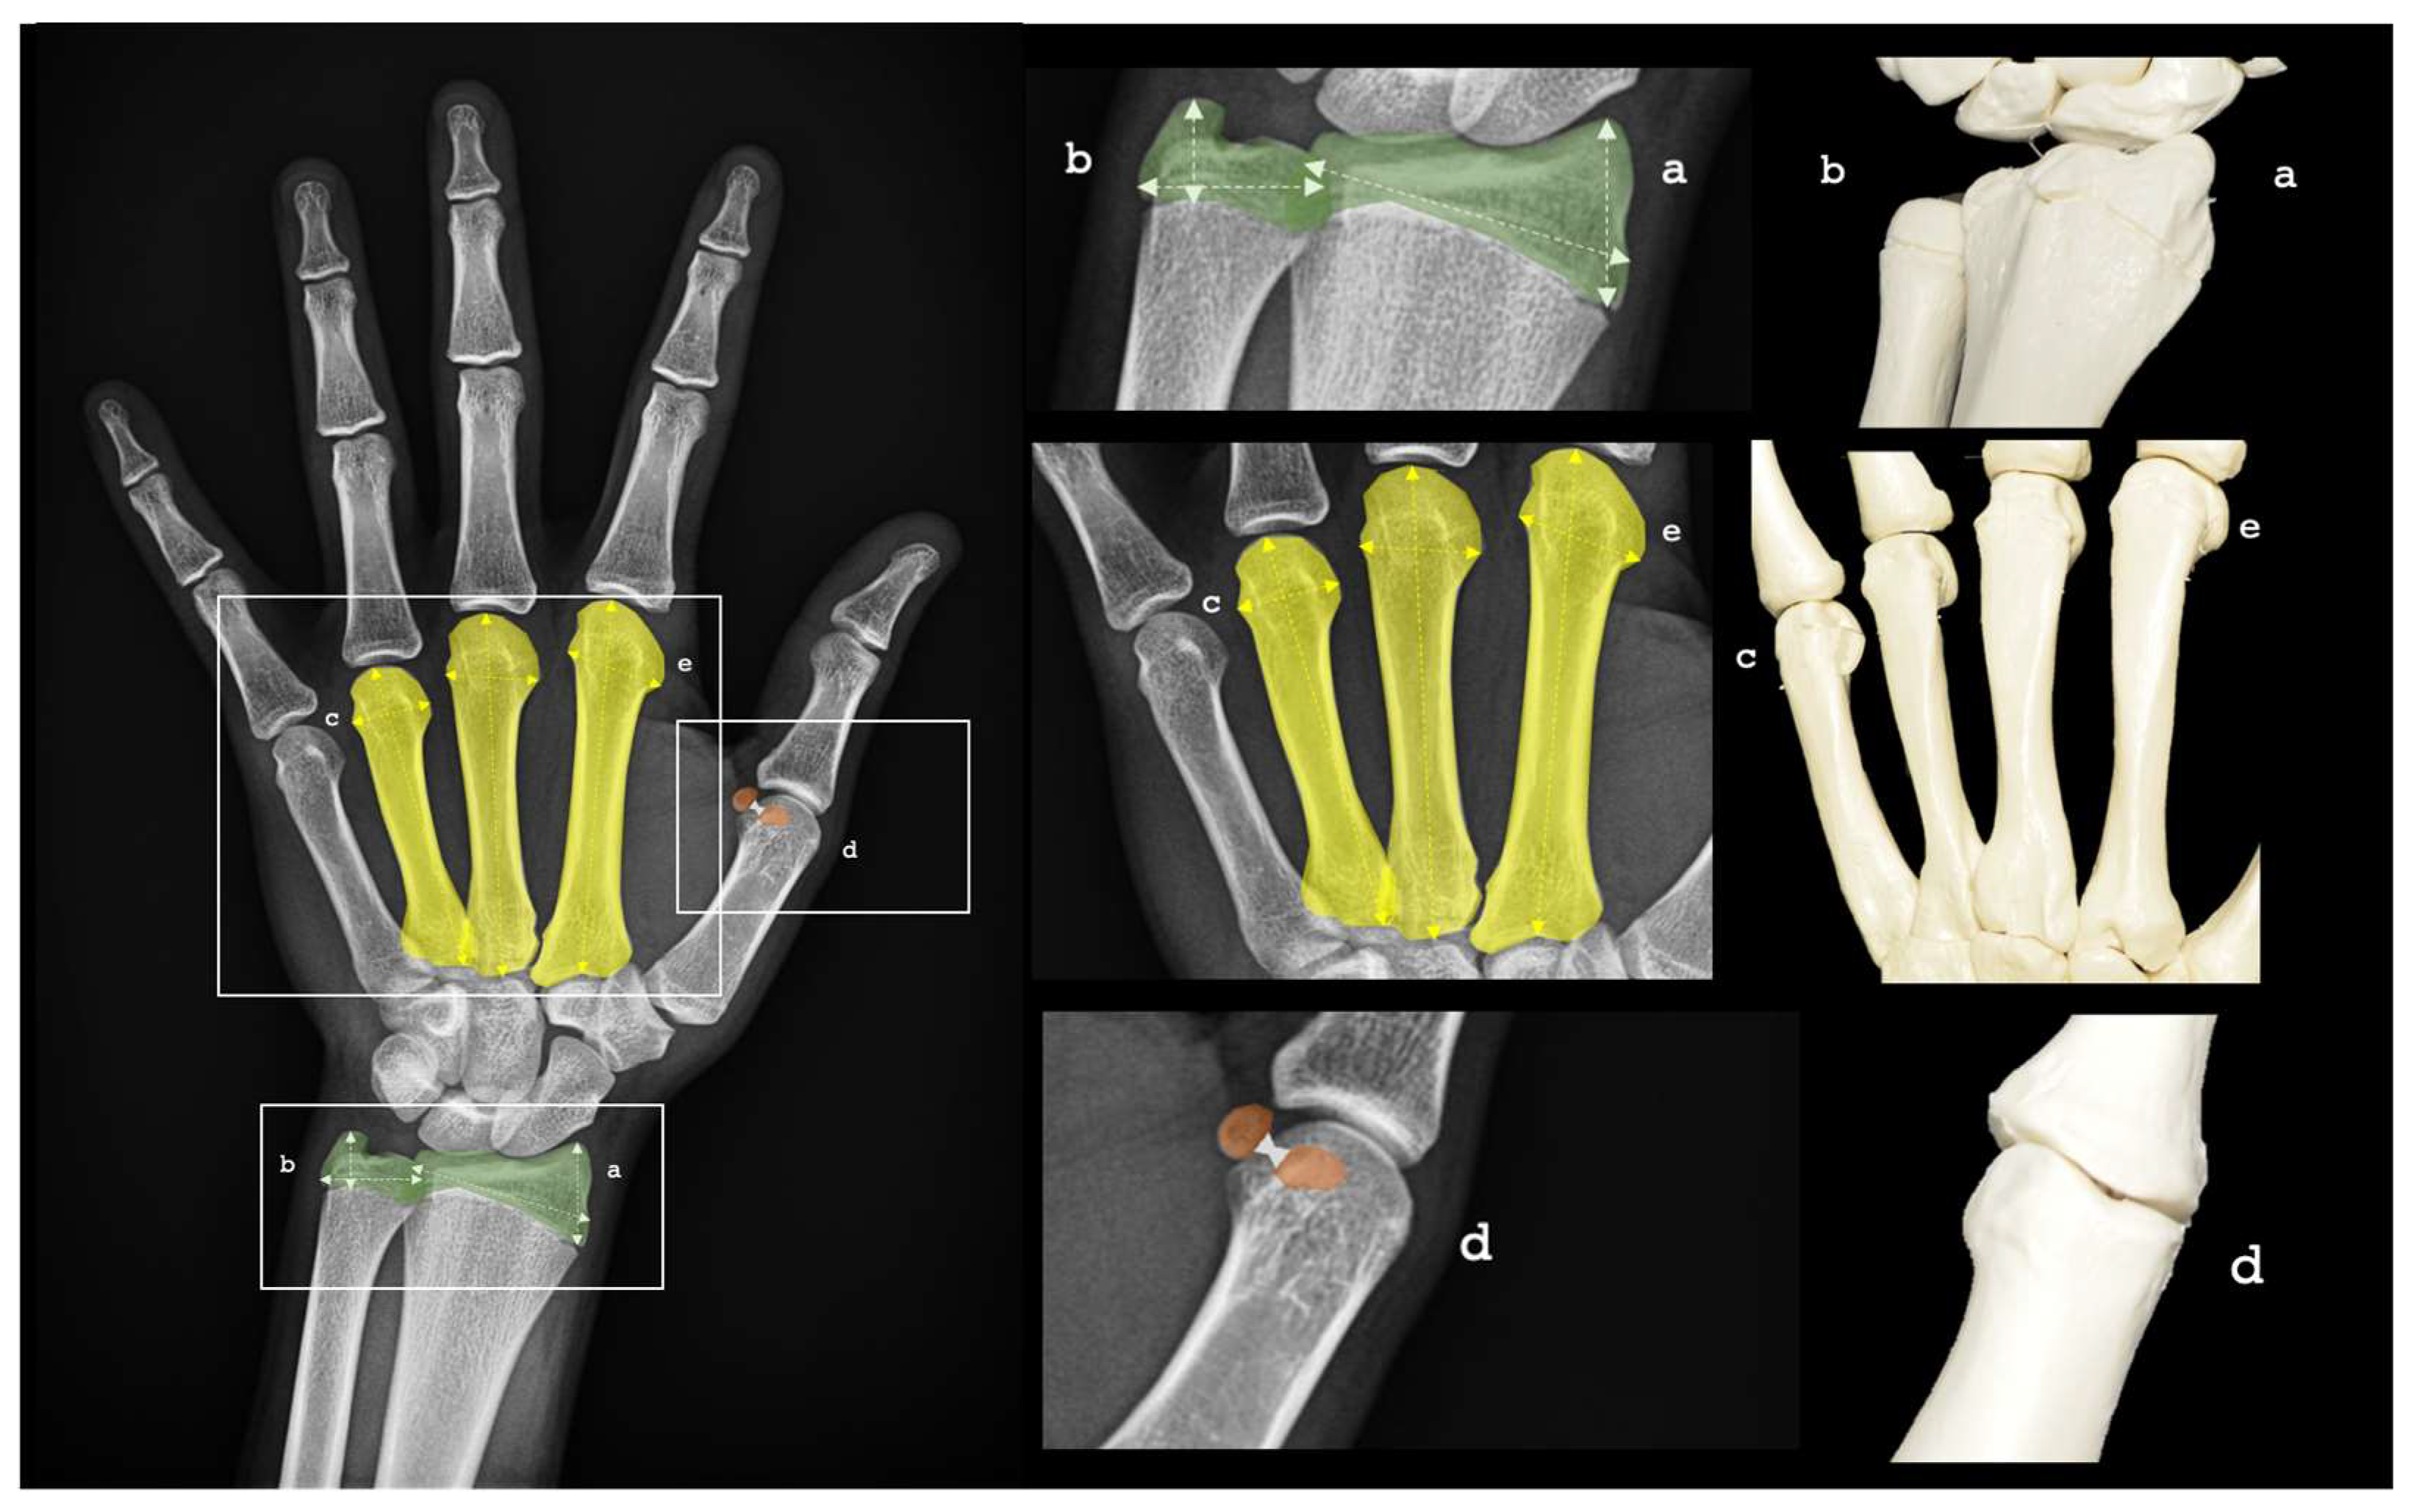

The regions of interest within each PA-HW radiograph were precisely outlined and assigned individual scores according to predefined criteria. Each radiograph underwent careful analysis, with detailed bone measurements meticulously recorded. Key parameters, captured using ImageJ (NIH, United States) [42], included: (a) radius length and width, (b) ulnar length and width, and (c) metacarpal length for digits 2, 3, and 4. In addition, essential metrics such as (d) intersesamoid distance and (e) epiphyseal width of metacarpals 2, 3, and 4 were systematically documented. These measurements, stored as pairs of bone descriptors and their corresponding numerical values, served as the foundation for the bone age estimation process. See more details in Figure 1.

Figure 1. PA-HW radiographs ROIs for BA assessment. (a) Radius length and width, (b) Ulnar length and width, (c) metacarpal length 2, 3, 4, (d) inter-sesamoid distance and (e) metacarpal epiphysis width 2, 3, 4 were systematically recorded. Source: Own work.